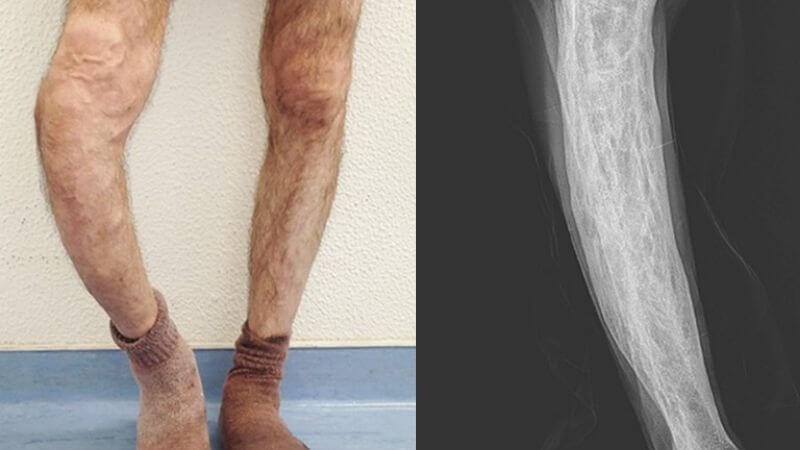

Bệnh lý về xương

Bệnh Paget (còn gọi là bệnh viêm xương biến dạng) là trường hợp điển hình nhất của các bệnh về xương không phải ung thư nhưng lại có nguy cơ phát triển thành u xương ác tính. Bệnh có các đặc tính như sau:

- Xương do bệnh này dày và nặng hơn nhưng yếu hơn so với xương khỏe mạnh.

- Bệnh không gây nguy đến tính mạng.

- Khoảng 1% bệnh nhân Paget kèm ảnh hưởng lên nhiều xương thì có thể mắc ung thư mô liên kết.